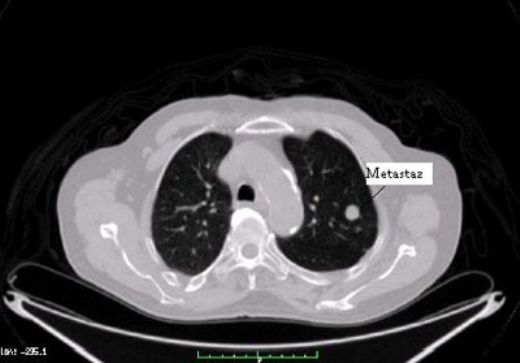

Akciğer Kanseri Metastaz Belirtileri ve Tedavisi Akciğer kanseri, dünya genelinde en sık görülen ve en ölümcül kanser türlerinden biri olup, genellikle erken evrelerinde belirgin semptomlar göstermemektedir. Ancak hastalık ilerledikçe, metastaz (kanserin vücudun diğer bölgelerine yayılması) belirtileri ortaya çıkmaktadır. Bu makalede, akciğer kanseri metastazının belirtileri ve tedavi yöntemleri detaylı bir şekilde ele alınacaktır. Akciğer Kanseri Metastaz Belirtileri Metastaz, akciğer kanserinin ilerlemesi ile birlikte farklı organlara ve dokulara yayılması anlamına gelir. Bu süreçte gözlemlenen bazı belirtiler şunlardır:

Metastazın Yayılma Alanları Akciğer kanseri, vücudun farklı bölgelerine metastaz yapabilir. Bu alanlar arasında: